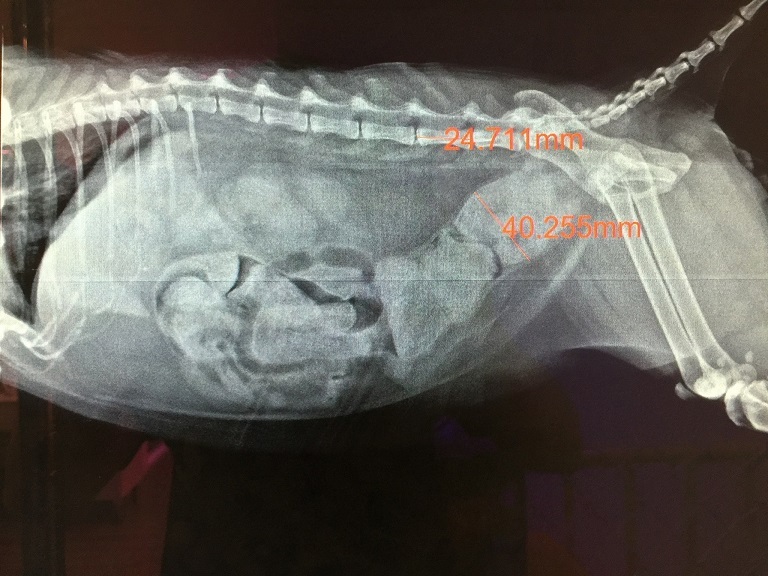

醫生在經過觸診檢查後,

說小黃可能已經積了一週多的大便在腸子裡,

刻不容緩需要立即進行麻醉浣腸,

將大量且硬梆梆的大便排出。

小黃累積在肚子裡的大便都已清出來,

醫生說小黃的大腸太粗、有巨結腸的情況,

導致大便較容易累積排不出,

且水也喝太少大便才會越來越硬。